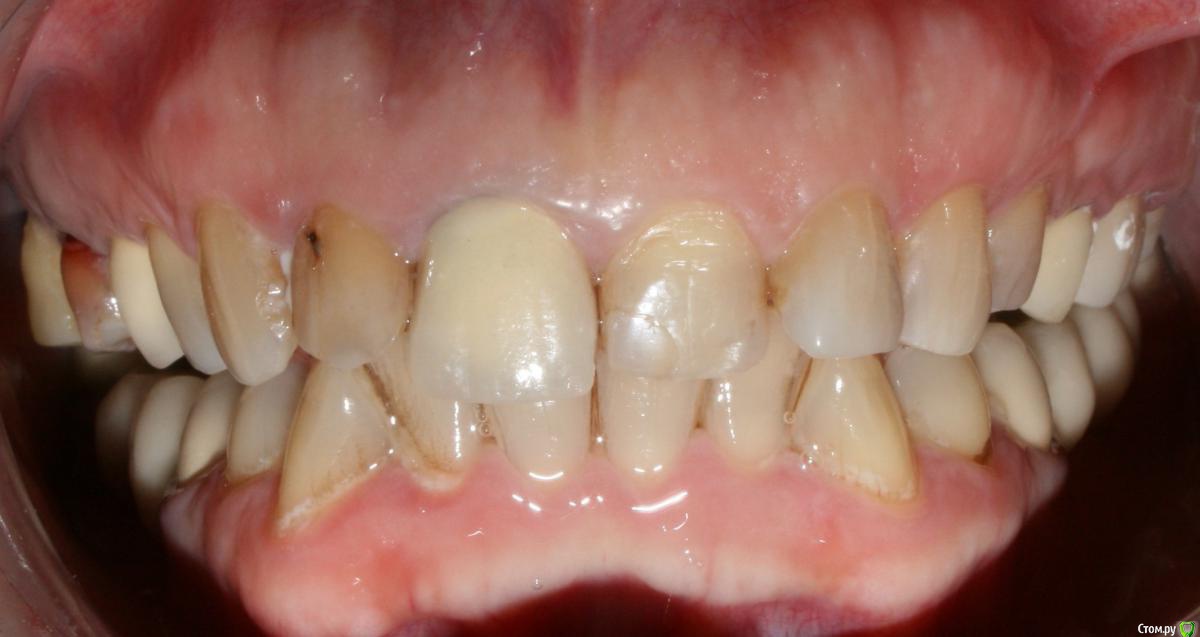

kramer Опубликовано 17 января, 2018 Поделиться Опубликовано 17 января, 2018 (изменено) Коллеги, добрый вечер. Помогите начинающему ортопеду. Заранее прошу простить за качество фото. Пациентка обратилась с целью улучшения эстетики фронтальных зубов. Около года назад один врач из нашей клиники делал м/к на боковые зубы (пациентку устраивают), при этом, по всей видимости, было снижение прикуса из-за стирания, но его высоту не восстанавливали. Теперь настало время передних зубов, и работать, получается, придется с имеющейся высотой. План лечения: 14, 24 - м/к, 13-23 имакс коронки/виниры. Меня смущают фасетки стираемости на клыках в/ч. Вопрос: каким образом лучше их реставрировать во избежание сколов реставраций? Делать полные коронки? Спасибо, надеюсь на ваш совет. Изменено 17 января, 2018 пользователем kramer Ссылка на комментарий

krokomot Опубликовано 17 января, 2018 Поделиться Опубликовано 17 января, 2018 Просится тотал, в случае, лайт варианта делайте все имах, везде показаны коронки, хотябы 3\4. Интересная концепция с зубом 1.1))) Ссылка на комментарий

kramer Опубликовано 18 января, 2018 Автор Поделиться Опубликовано 18 января, 2018 Просится тотал, в случае, лайт варианта делайте все имах, везде показаны коронки, хотябы 3\4. Интересная концепция с зубом 1.1)))Спасибо. 11 сделан в каких-то махровых годах. Вариант с винирами отпадает по функциональным или эстетическим причинам? Ссылка на комментарий

krokomot Опубликовано 18 января, 2018 Поделиться Опубликовано 18 января, 2018 Спасибо. 11 сделан в каких-то махровых годах. Вариант с винирами отпадает по функциональным или эстетическим причинам?По объему сохранившихся тканей у зубов Ссылка на комментарий

StomV Опубликовано 22 января, 2018 Поделиться Опубликовано 22 января, 2018 Я не пойму,почему все в один голос твердят,что здесь нужно поднимать прикус?Какие показания? С чего вы это решили?Нужно исходить из возраста пациента. Да здесь видны фасетки стираемости,но не стоит забывать,что есть еще компенсация стираемости в виде роста альвеолярного отростка с зубами (гипертрофия) и далеко не всегда стираемость приводит к снижению МАВ. Здесь как раз намного важнее определиться с ЦС и ВНЧС,как минимум провести тесты,сделать КТ сустава.Если все в норме,то нет нужны поднимать высоту. Я думаю в данной клинической ситуации возможно отмоделировать достточно неплохо фронт,хотелось бы увидеть ваш вариант воска. 1 Ссылка на комментарий